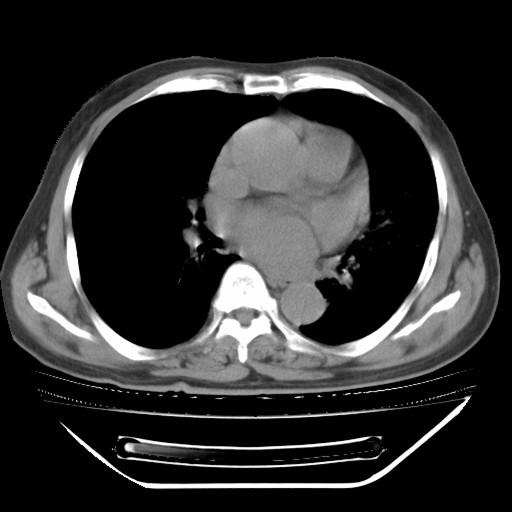

以下是引用hhcckk在2009-5-29 10:34:00的发言:[br]左下肺片絮状边缘模糊影,考虑感染,建议治疗后复查[br]